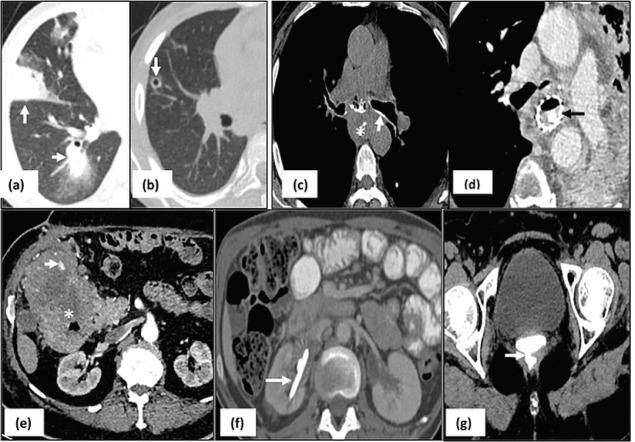

A total of 14,226 CT scans were performed during the study period, out of which 599 patients had CrC. Most of the CrC were seen involving thorax (265/599, 44.3%) followed by abdomen (229/599, 38.2%) and head and neck (104/599, 17.3%) regions. The commonly encountered CrC were pulmonary infections, superior vena cava obstruction and drug-induced lung changes.

在研究期间共进行了14226次CT扫描,其中599例患者有CrC。大多数CrC见于胸部(265/599,44.3%),其次是腹部(229/599,38.2%)和头颈部(104/599,17.3%)区域。常见的CrC包括肺部感染、上腔静脉阻塞和药物性肺改变。